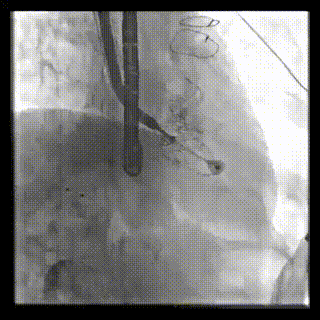

2021年12月24日,復(fù)旦大學(xué)附屬中山醫(yī)院葛均波院士團隊成功應(yīng)用LuX-Valve Plus為一例極重度三尖瓣反流(TR)合并房顫、房缺的患者完成了經(jīng)血管三尖瓣置換術(shù),這是在前基礎(chǔ)上,本周完成的第三例經(jīng)血管三尖瓣置換手術(shù),葛均波院士、周達新教授等與心外科魏來教授、賴顥教授,心超室的潘翠珍教授、李偉教授及麻醉科的郭克芳教授共同完成了本周手術(shù),均獲得圓滿成功!患者術(shù)后超聲顯示無TR,臨床癥狀明顯改善。本周手術(shù)的成功也為LuX-Valve Plus救治性臨床研究添上了濃墨重彩的一筆。

本周三例接受LuX-Valve Plus經(jīng)血管三尖瓣置換術(shù)的患者中,第一例患者為冠狀動脈旁路移植術(shù)+Bentall+二尖瓣成形術(shù)后;第二例患者為永久起搏器植入術(shù)后,存在跨三尖瓣導(dǎo)線;第三例患者合并房顫、房缺及左心耳封堵術(shù)后。

三例患者入院后,葛均波院士團隊周達新教授、潘文志教授、張源博士、陳莎莎博士及心超室的潘翠珍教授、李偉教授對患者的情況進行詳細評估和討論,最終決定為三例患者選擇LuX-Valve Plus40mm、50mm和50mm型號的瓣膜進行手術(shù)治療。手術(shù)后即刻拔除氣管插管,術(shù)后患者三尖瓣反流癥狀得到顯著改善,復(fù)查心超結(jié)果顯示人工三尖瓣瓣膜支架固定穩(wěn)定,瓣葉關(guān)閉形態(tài)未見異常,未見明顯反流。